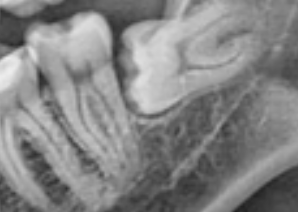

아래쪽에 수평매복 사랑니 갖고있습니다.

그림처럼 사랑니하고 왼쪽 어금니 사이에 뼈가 거의 없고, 앞치아가 건강한 상태인데도 불구하고

뽑고 나면 뼈가 안차오를거라고 합니다.